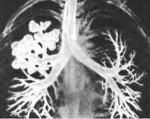

При бронхографии обнаруживаются многочисленные четкообразные и веретеновидные расширения сегментарных и более мелких бронхов в верхних отделах легких и шарообразные - в нижних отделах. На диагностической бронхоскопии определяются признаки катарального или гнойного эндобронхита, деформация устьев долевых и сегментарных бронхов, уменьшение дыхательной подвижности.